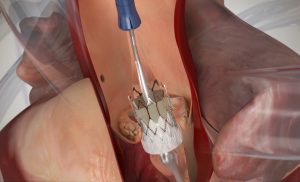

La technique conventionnelle avec circulation extracorporelle reste, à l‘heure actuelle, l‘intervention de référence la plus souvent utilisée pour les patients en bon état général et jusqu’à un certain âge. Cependant depuis 2002, une méthode par cathéter a été développée, permettant de remplacer la valve aortique sans ouverture du sternum et sans utilisation de la circulation extracorporelle. Lors de cette méthode, sous anesthésie locale, un cathéter est introduit dans une des grandes artères, par exemple, en région inguinale directement dans l‘artère fémorale, ou en alternative, dans l‘artère sous-claviculaire. Ce cathéter est passé le long de cette artère jusqu‘au niveau de la valve aortique malade, qui est dilatée à l‘aide d‘un ballonnet gonflable. Un stent avec une nouvelle valve biologique est ensuite placé dans l‘annulus de la valve aortique. Cette technique peut également se faire par un accès direct au cœur, en pratiquant une incision de 5 cm de longueur au niveau du thorax. Cette méthode, qui est appelée TAVI, est beaucoup moins invasive qu‘une intervention à coeur ouvert habituelle.

Mais elle présente aussi quelques désavantages : Après TAVI, des stimulateurs cardiaques (pacemaker) doivent plus souvent être implantés, car le système de conduction du cœur peut être endommagé lors de cette procédure. De plus, des fuites peuvent survenir près de la nouvelle stent-prothèse, et ces fuites, appelées insuffisances para valvulaires, peuvent endommager le muscle cardiaque.

Il n’y a pas encore de résultats à long terme sur la longévité de ce type de bio prothèses valvulaires.

Avec les nouvelles générations de prothèses TAVI, utilisées à l’INCCI, ces complications sont mieux contrôlées. De nos jours, on recommande donc cette méthode moins invasive chez les patients plus âgés et très malades, chez lesquels une opération traditionnelle présente trop de risques ou est devenue impossible.